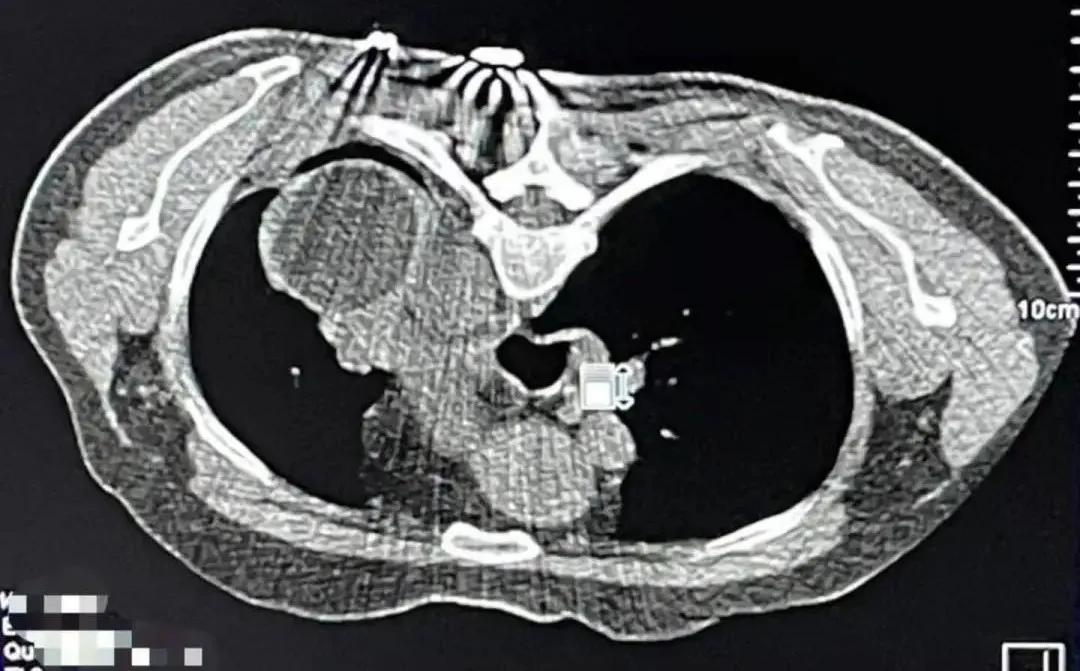

4月7日,重庆大学附属肿瘤医院中医肿瘤治疗中心顺利完成与北京中医药大学东方医院合作的国家重点研发计划项目——Ⅲb/Ⅳ非小细胞肺癌(NSCLC)绿色治疗方案的多中心随机对照临床研究第二例患者。该患者62岁,肺癌ⅥA期,经过冷冻消融技术治疗后冰球全部覆盖肿瘤,并且肿瘤已经出现局部坏死现象,治疗取得阶段性进展。